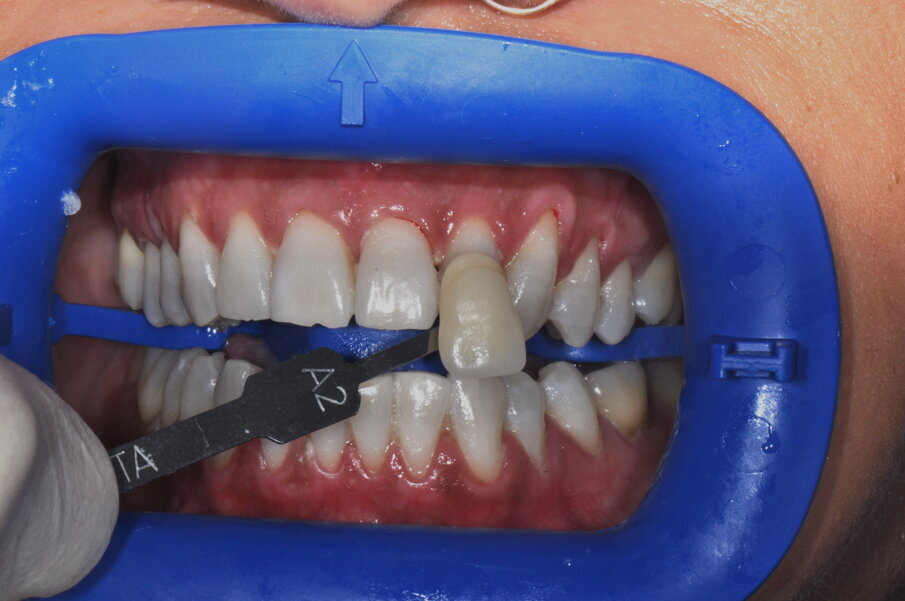

Fig. 6 - Fotografia frontale scattata prima della seduta di igiene orale professionale (Guided Biofilm Therapy).

Fig. 7 - Fotografia frontale scattata dopo la seduta di igiene professionale mediante l’utilizzo del sistema Airflow® Prophylaxis Master (EMS®) con polvere a base di eritritolo® e ablatore a ultrasuoni con punta perioslim (PS, EMS®).

Fig. 8 - Rilevamento del colore a tempo zero utilizzando la scala “Vita” D3.

Fig. 9 - Colore post sbiancamento professionale utilizzando la scala “Vita” A2.